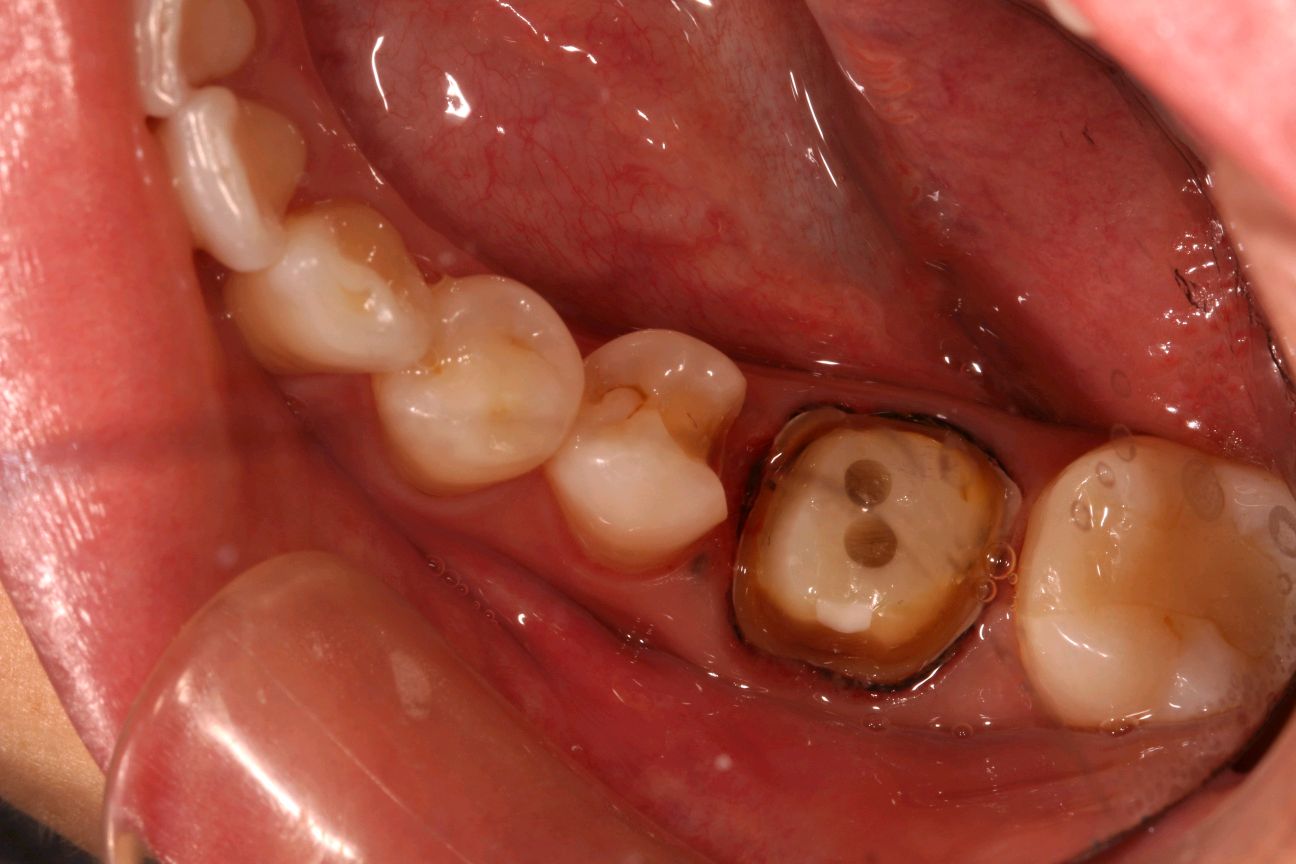

术中拆冠后

图片发自160App

进行 46 牙 纤维桩植入,45 牙旧充填物去除